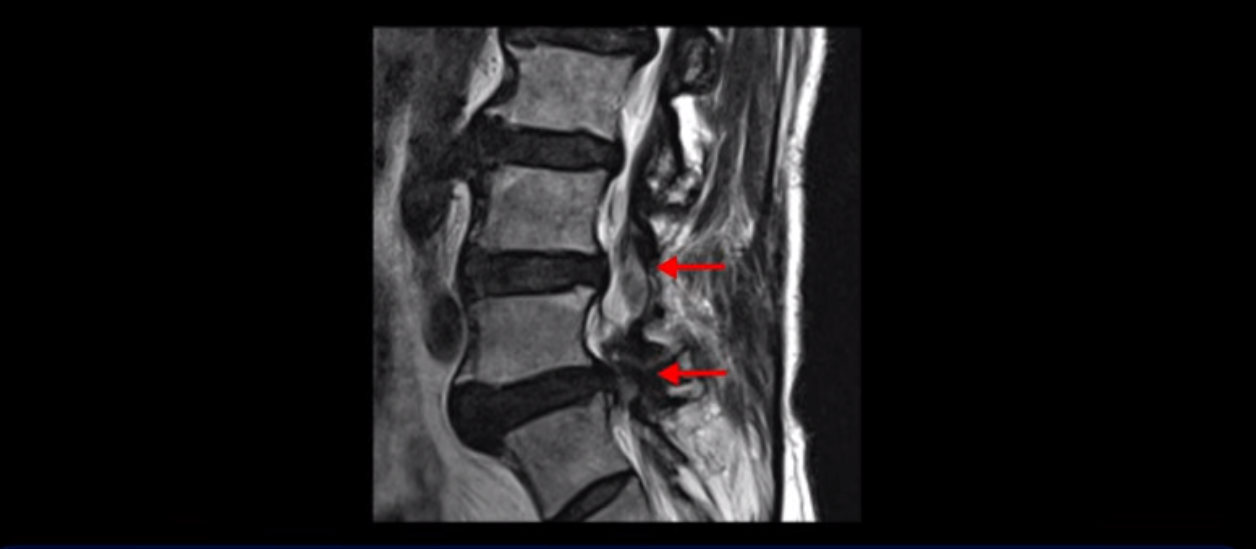

이분은 허리 다섯 마디 중 4번 5번, 5번 1번에 감압술로 눌린 신경을 풀어주는 수술을 받았습니다.

5번 1번도 왼쪽 후궁을 열고 수술 받았습니다.

하지만 중심성 협착은 여전히 심한 상태입니다.

이분은 오른쪽, 왼쪽 다리에 모두 방사통이 심하고 왼쪽 다리에 마비 증상, 즉 풋드랍(족하수) 증상이 있습니다. 왼쪽 신경 가지가 빠져나가는 추간공을 보면 두 마디가 좁아져 있습니다.

이런 신경 구멍이 좁아져 있는 걸 협착이라고 합니다.

이미 앞선 두 번의 수술로 뼈와 인대 등을 일부 제거해서 안정성이 떨어진 상태에서 추가로 수술하려니까 척추가 너무 불안정해져 무너질 게 걱정되니까 이번에는 나사 박는 유합술을 권유 받은 겁니다. 이런 환자분들의 방사통과 마비 증상이 어떻게 수술 없이 좋아질 수 있을까요? 치료는 어떻게 하는 걸까요?